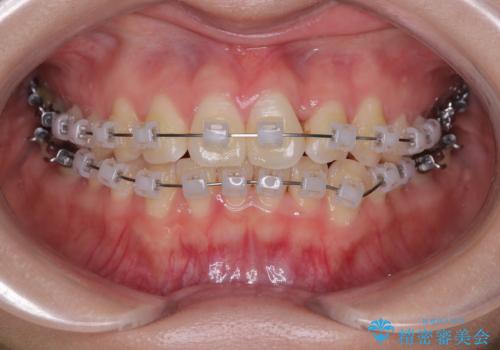

治療方法としては、装置の目立ちにくさと費用面のバランスを考慮して、プラスチック製のクリアブラケットとメタルワイヤーを組み合わせた矯正装置を使用することにしました。

矯正治療期間はわずか10か月と、比較的短期間で終了しました。